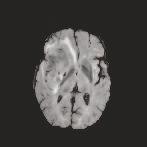

Multi-modal medical image completion has been extensively applied to alleviate the missing modality issue in a wealth of multi-modal diagnostic tasks. However, for most existing synthesis methods, their inferences of missing modalities can collapse into a deterministic mapping from the available ones, ignoring the uncertainties inherent in the cross-modal relationships. Here, we propose the Unified Multi-Modal Conditional Score-based Generative Model (UMM-CSGM) to take advantage of Score-based Generative Model (SGM) in modeling and stochastically sampling a target probability distribution, and further extend SGM to cross-modal conditional synthesis for various missing-modality configurations in a unified framework. Specifically, UMM-CSGM employs a novel multi-in multi-out Conditional Score Network (mm-CSN) to learn a comprehensive set of cross-modal conditional distributions via conditional diffusion and reverse generation in the complete modality space. In this way, the generation process can be accurately conditioned by all available information, and can fit all possible configurations of missing modalities in a single network. Experiments on BraTS19 dataset show that the UMM-CSGM can more reliably synthesize the heterogeneous enhancement and irregular area in tumor-induced lesions for any missing modalities.